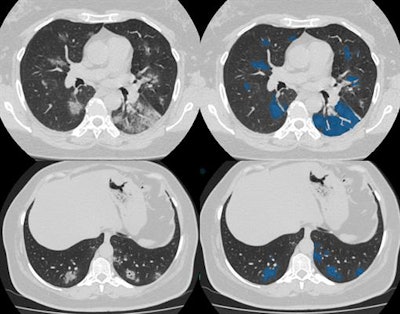

"The study from the scanner is transferred to URIS right away and processed by algorithms. Then a radiologist receives both the original image and the image processed by AI. The doctor opens a worklist of studies on his/her computer which need to be interpreted. Preliminary study markings of suspected pathology made by AI services are available to a specialist," he said.

"When a radiologist opens CT scan images, he/she sees a copy of the original image, on which AI has highlighted pathological findings in red. This is how the algorithm draws the doctor's attention to the lung areas with a probable lesion," he continued. "To help with interpretation, AI can generate a report where it indicates the probability of viral pneumonia."

From 13 April to 20 June, staff conducted over 170,000 chest CT scans at Moscow's 48 outpatient CT centers. All images courtesy of Prof. Sergey Morozov and Ilya Egorov.

From 13 April to 20 June, staff conducted over 170,000 chest CT scans at Moscow's 48 outpatient CT centers. All images courtesy of Prof. Sergey Morozov and Ilya Egorov.All cases of COVID-19 pneumonia have the following distribution by the degree of detected findings: CT-1 (mild), more than 49,000 cases (60%); CT-2 (moderate), more than 24,000 (29%); CT-3 (severe), more than 8,000 (10%); CT-4 (critical), more than 750 (1%).